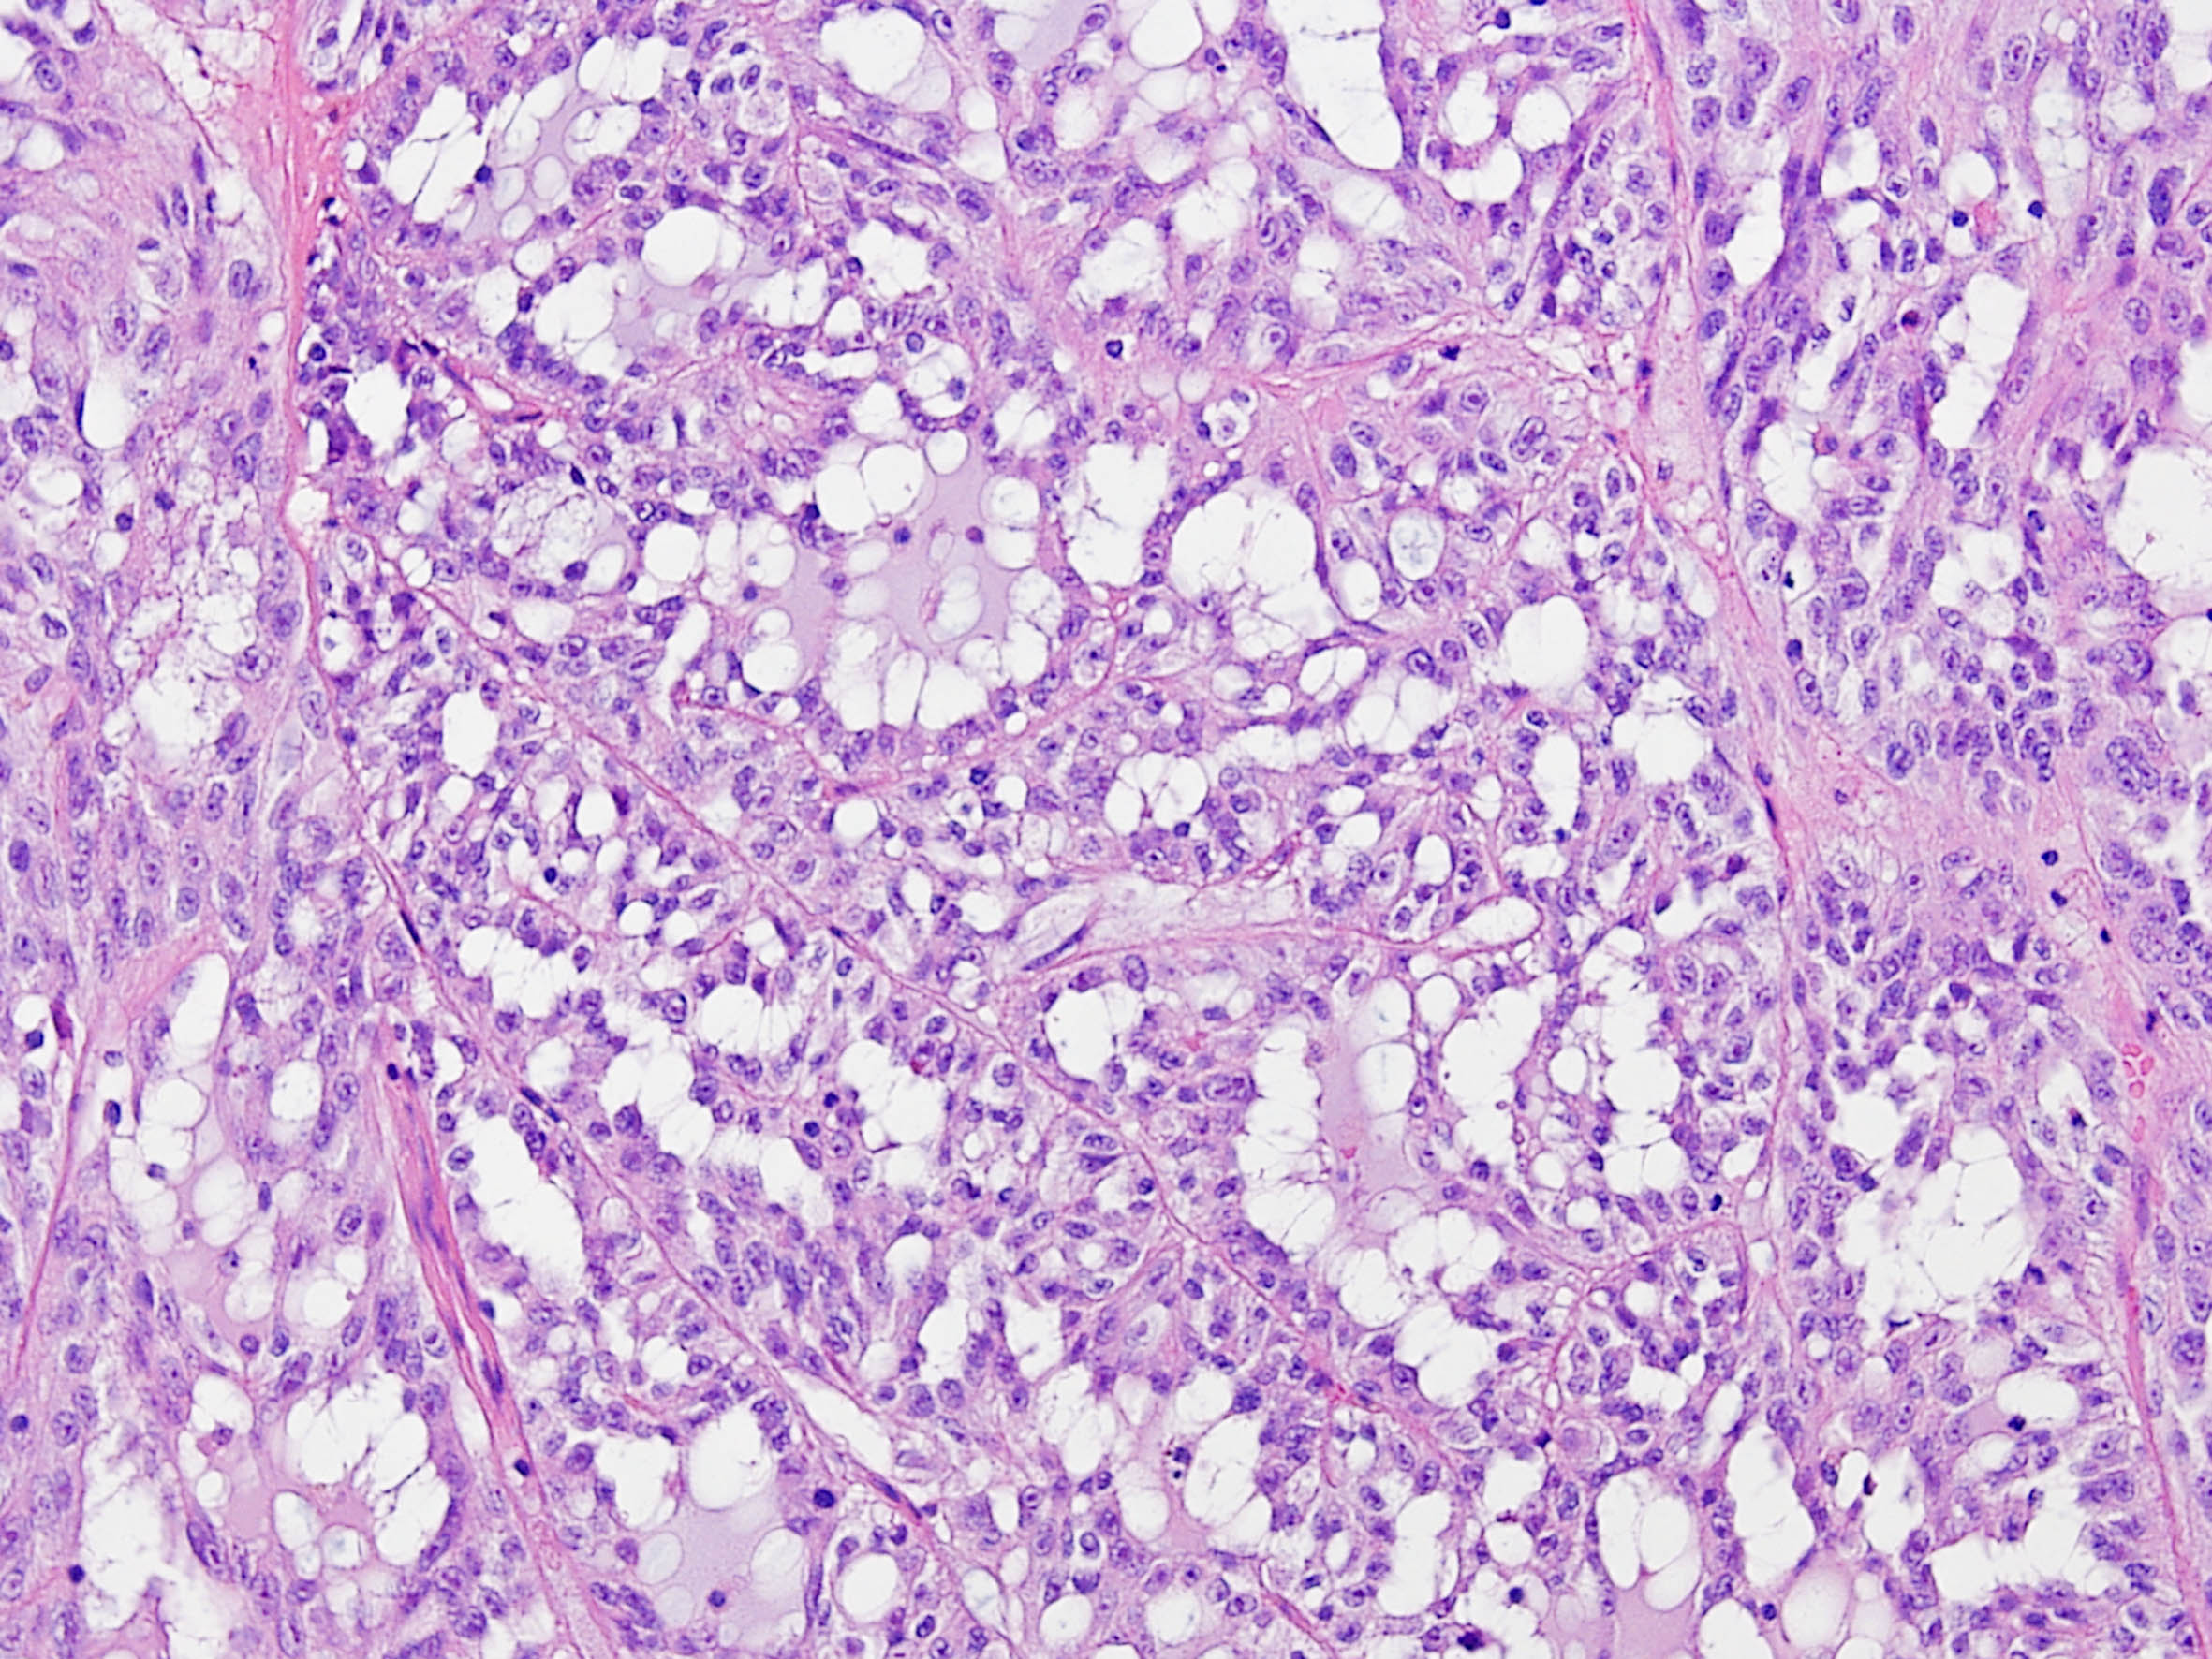

Classification of renal tumors

Case ID: 171